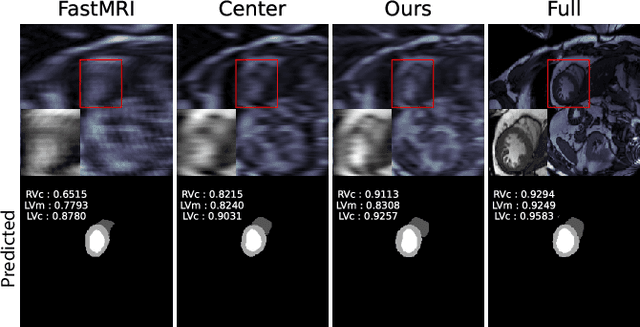

Abstract:To accelerate MRI, the field of compressed sensing is traditionally concerned with optimizing the image quality after a partial undersampling of the measurable $\textit{k}$-space. In our work, we propose to change the focus from the quality of the reconstructed image to the quality of the downstream image analysis outcome. Specifically, we propose to optimize the patterns according to how well a sought-after pathology could be detected or localized in the reconstructed images. We find the optimal undersampling patterns in $\textit{k}$-space that maximize target value functions of interest in commonplace medical vision problems (reconstruction, segmentation, and classification) and propose a new iterative gradient sampling routine universally suitable for these tasks. We validate the proposed MRI acceleration paradigm on three classical medical datasets, demonstrating a noticeable improvement of the target metrics at the high acceleration factors (for the segmentation problem at $\times$16 acceleration, we report up to 12% improvement in Dice score over the other undersampling patterns).